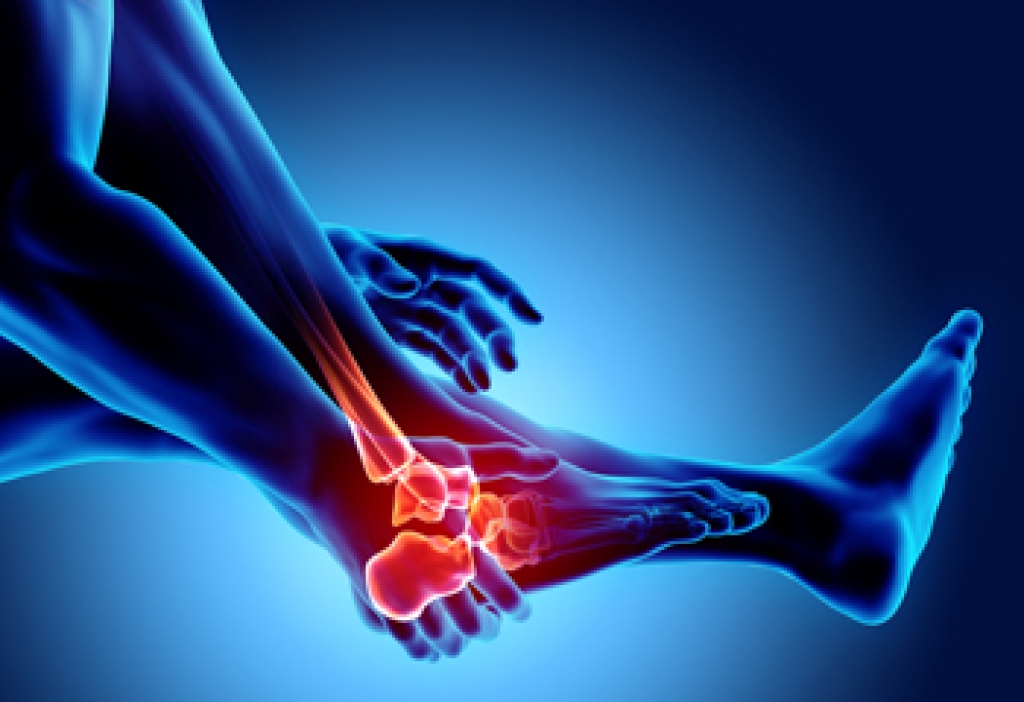

Arthritis is a form of joint inflammation that can find its way into the feet, bringing discomfort and challenges to mobility. Osteoarthritis, often linked to wear and tear, can lead to pain and stiffness in the foot's joints. Rheumatoid arthritis, an autoimmune disorder, can cause painful swelling and deformities. Gout, characterized by sudden, intense pain, emerges from uric acid buildup. Relief options encompass a range of strategies. Wearing custom orthotics, which offer cushioning and support, can help to reduce pressure on affected areas. Stretches and exercises can enhance flexibility and strength. Medications, including anti-inflammatories, can be beneficial in providing relief. Lifestyle adjustments, such as weight management and choosing proper footwear, can also alleviate symptoms. Consulting a podiatrist ensures a tailored approach to managing arthritis in the feet. If you have any type of foot arthritis, it is suggested that you contact this type of doctor who can offer you effective relief options.

Arthritis is a joint disorder that involves the inflammation of different joints in your body, such as those in your feet. Arthritis is often caused by a degenerative joint disease and causes mild to severe pain in all affected areas. In addition to this, swelling and stiffness in the affected joints can also be a common symptom of arthritis.